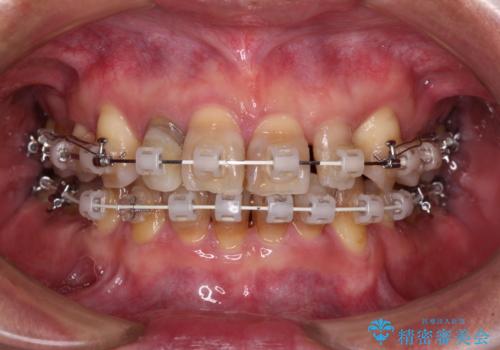

左右に骨格がずれて咬みにくい ワイヤー装置による抜歯矯正

- 骨格的な咬み合わせのズレ、前歯のデコボコとクロスバイトを気にして来院された患者様です。

全額的にデコボコが強いため、上下左右の小臼歯計4歯を抜歯し、ワイヤー装置による矯正治療を行うこととしました。

抜歯する歯の一部をセオリーである第一小臼歯ではなく、第二小臼歯にすることで、骨格的なずれをカバーするように計画しました。

小臼歯の抜歯する部位を選択したことで、安定した咬み合わせとなりましたが、第二小臼歯を抜歯した部分はスペースを閉じるのに長い期間を要しました。

矮小歯であった上顎前歯2本は、矯正治療後にバランスの取れた大きさのオールセラミッククラウンを装着しました。